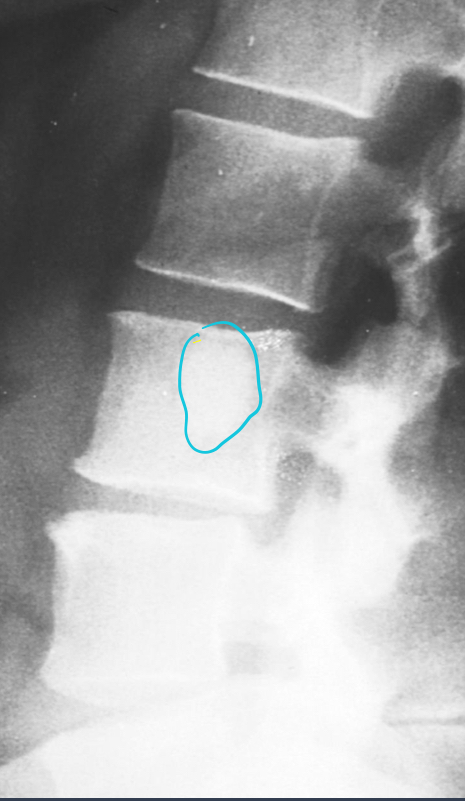

what is this?

enlarged IVF

neurofibromatosis